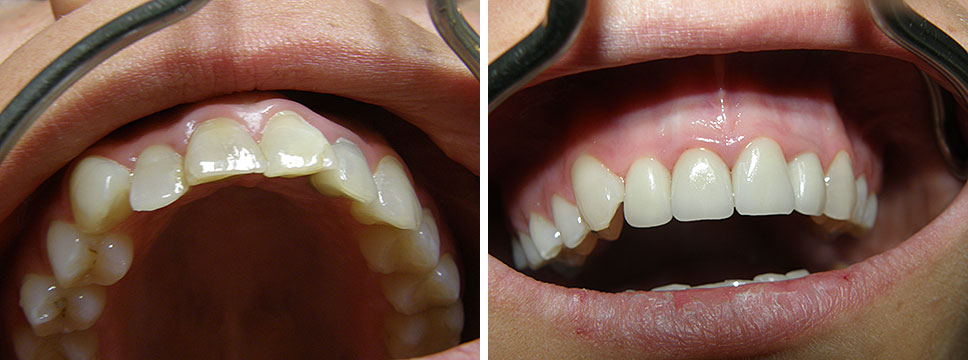

Estetska dentalna medicina